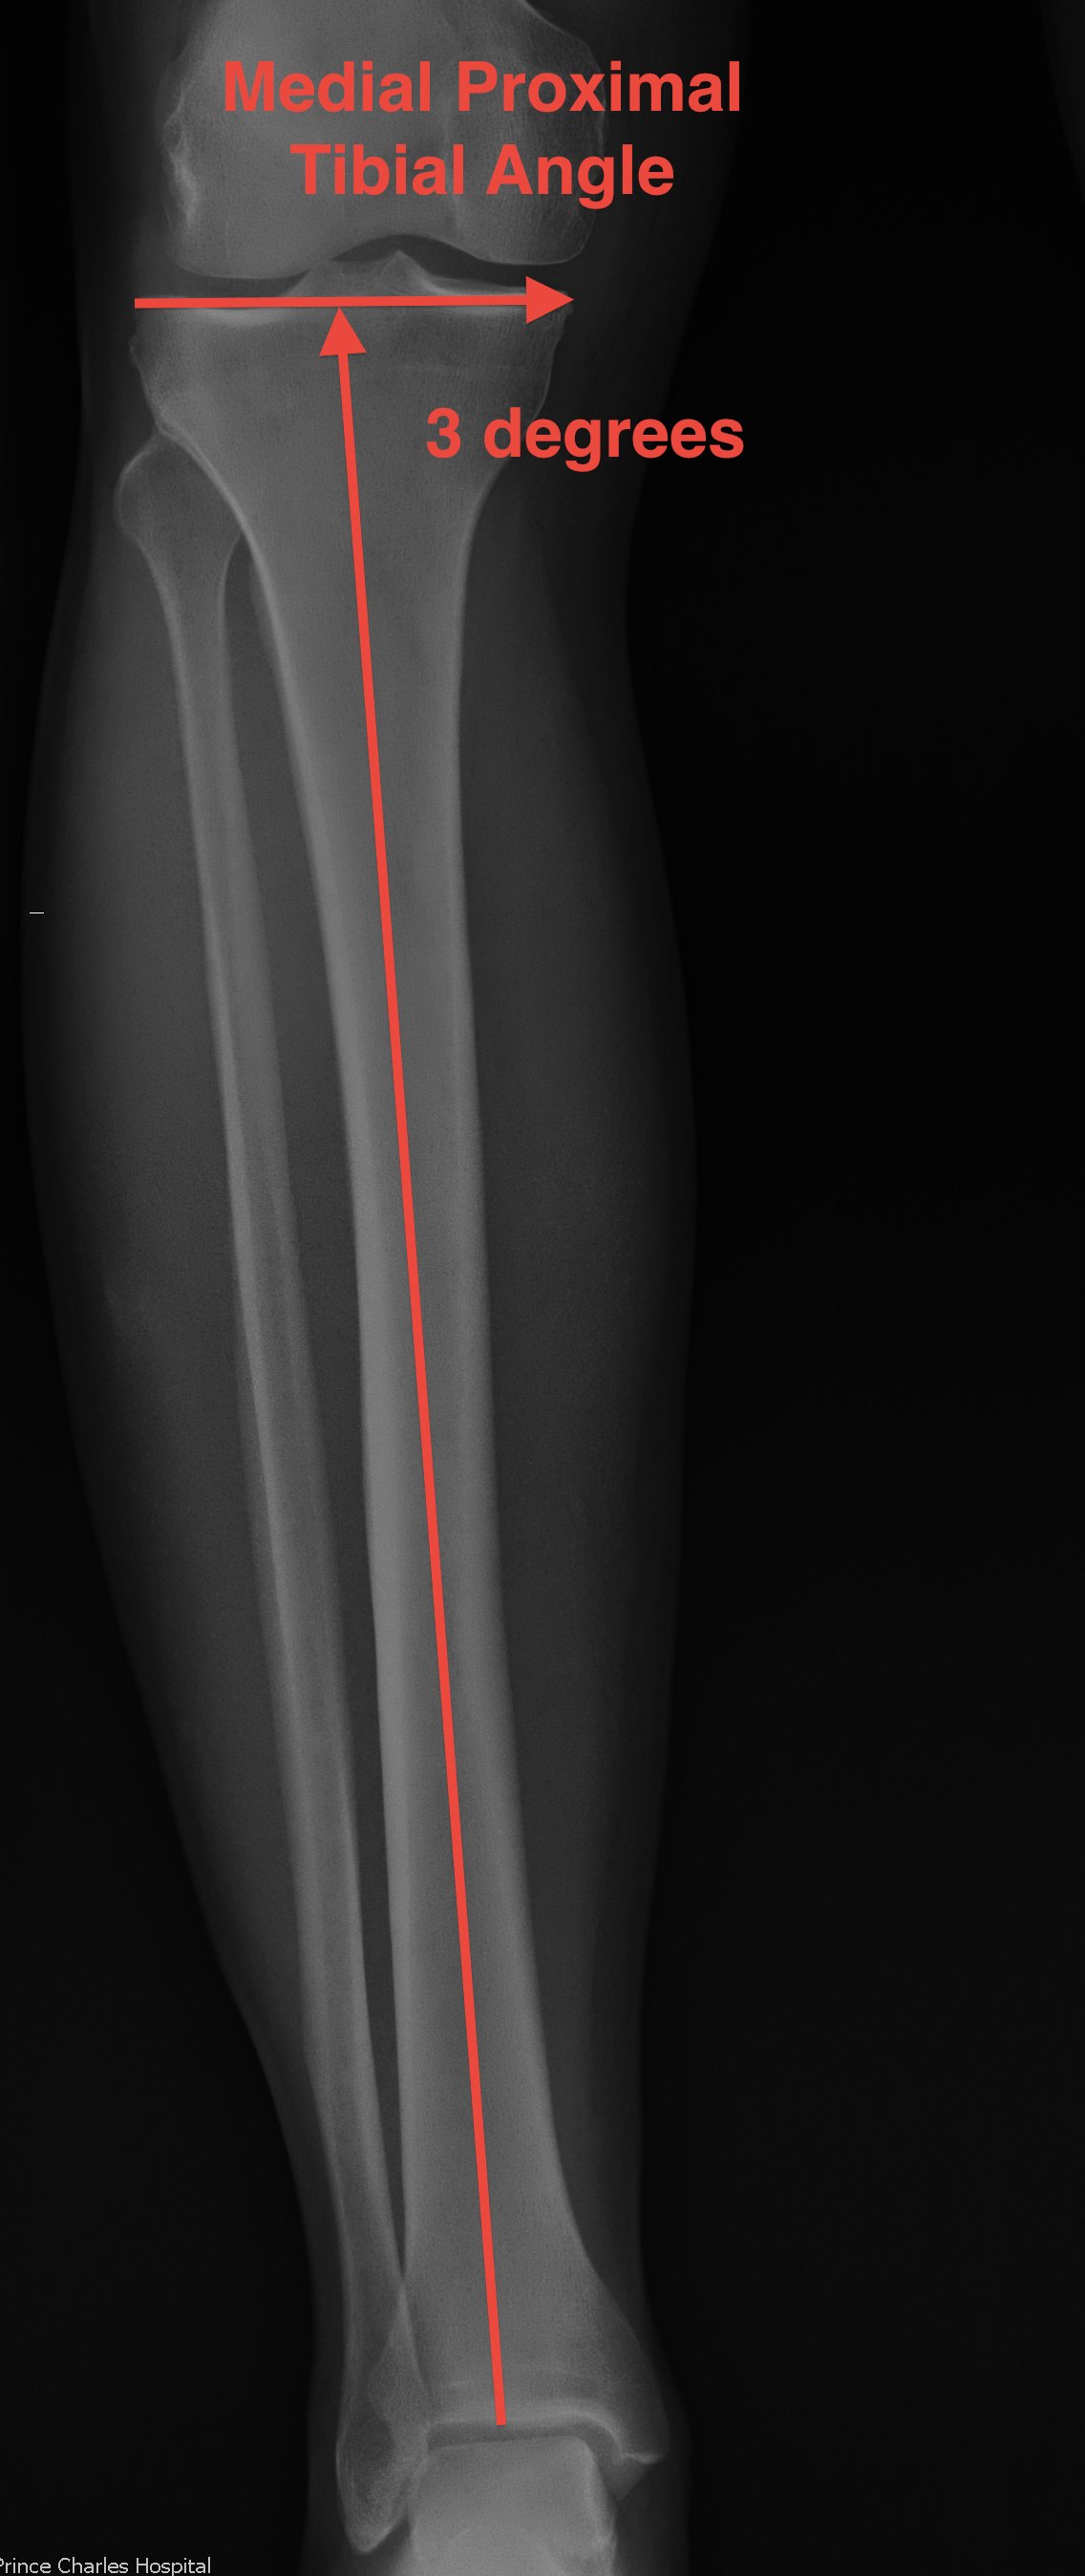

Anatomical axis Tibia (AAT)

- centre of tibia to proximal joint line

- normally 3o varus

- medial proximal tibial angle 87˚